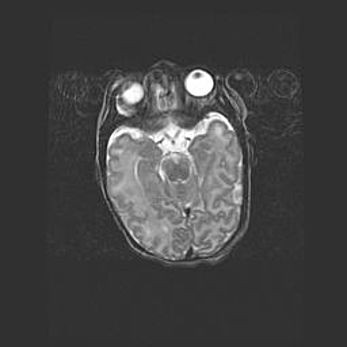

Неполная лизэнцефалия (пахигирия). Открытая гидроцефалия.

Возраст: 17 дней

Вес: 3110 г

Пол: мужской

Окружность головы: 33,5 см

Срок гестации: 35-36 недель

Лизэнцефалия—недоразвитие корковой пластинки и мозговых извилин в результате нарушения миграции нейронов коры. Поверхность мозговых полушарий гладкая. Микроскопически выявляется отсутствие нормальных слоев коры и скопление групп нейронов в подкорковом белом веществе.

Пахигирия—уменьшение числа вторичных извилин. В пораженном полушарии нервные клетки образуют толстый недифференцированный слой с неправильно расположенными нервными волокнами и группами гетеротопных клеток. Нервные клетки незрелые. Белое вещество истончено. При этом нередко аномально развит корково-спинномозговой путь.